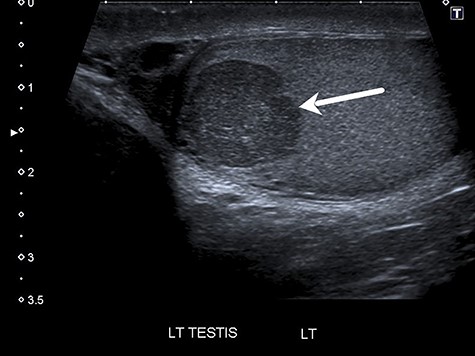

Scrotal ultrasound identified a 14 × 12-mm hypoechoic mass towards the upper pole of the left testis (Fig. 1) reported as suspicious for an intratesticular neoplasm. A 2-cm simple cyst of the left epididymis was also reported. The right testis was normal.

Ultrasound showing 14 × 12-mm hypoechoic mass in the upper pole of the left testis (see arrow).